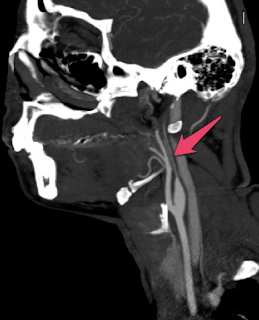

Tomografia MIP, plano sagital com hipoplasia da artéria carótida interna esquerda.